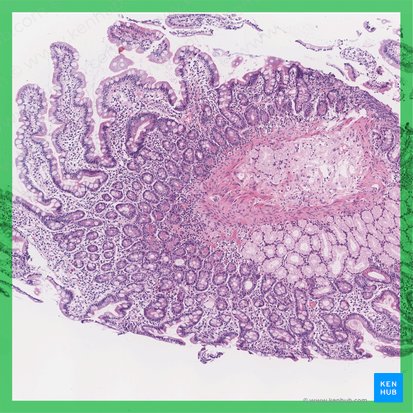

Histológicamente, el duodeno es bastante similar a todos los órganos huecos del tracto gastrointestinal: mucosa, submucosa y la túnica muscular.

- La mucosa está conformada por un epitelio cilíndrico simple (lámina epitelial), una capa de tejido conectivo (lámina propia) y una capa de músculo liso (lámina muscular). Las células epiteliales intestinales (enterocitos) están recubiertas por una capa de glicoproteínas y mucina.

- La submucosa está constituida por tejido conectivo laxo, varios vasos sanguíneos y el plexo de Meissner.

- La capa muscular está formada por una musculatura circular interna y otra longitudinal externa entre las que podemos encontrar al plexo de Auerbach.

En todas las porciones del intestino delgado es típico observar microvellosidades (estructuras en forma de pelos que sobresalen de la superficie), las vellosidades con forma de dedos y los pliegues circulares de la mucosa y submucosa (válvulas de Kerckring). Estas estructuras aumentan el área de absorción del duodeno hasta unas 1500 veces.

El duodeno es rico en enterocitos absorbentes, células caliciformes productoras de moco y células endocrinas productoras de hormona peptídica.

Una característica clave del duodeno son las glándulas de Brunner las cuales se encuentran en la submucosa. Estas glándulas producen moco que contiene bicarbonato el cual sirve para neutralizar al ácido gástrico (sin esta neutralización, es común ver pacientes con úlceras duodenales) Asimismo, entre las vellosidades se encuentran las criptas de Lieberkühn. La células de Paneth se encuentran en el lumen de estas criptas. Según lo que se conoce hasta ahora, las células de Paneth juegan un papel importante en cuanto a la defensa antimicrobiana, sin embargo es importante mencionar que sus funciones aún no son totalmente conocidas.